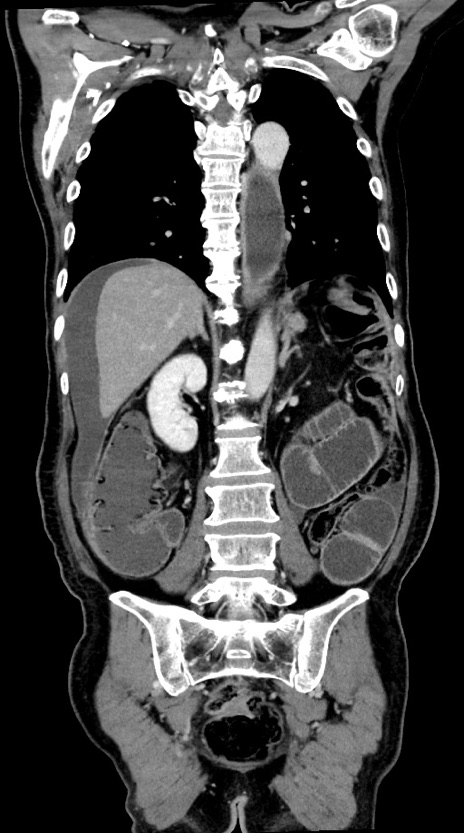

症例28(冠状断像)

【症例】60歳代男性

【主訴】嘔吐

【現病歴】胃癌にて胃全摘後。食思不振が悪化し、夜中に嘔吐することがある。

【既往歴】胃癌、胃全摘、脾摘、胆摘後

【データ】WBC 5900、CRP 10.56